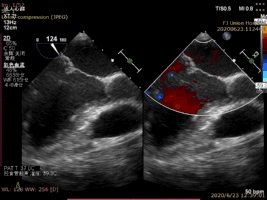

病例2术后二尖瓣反流为轻度